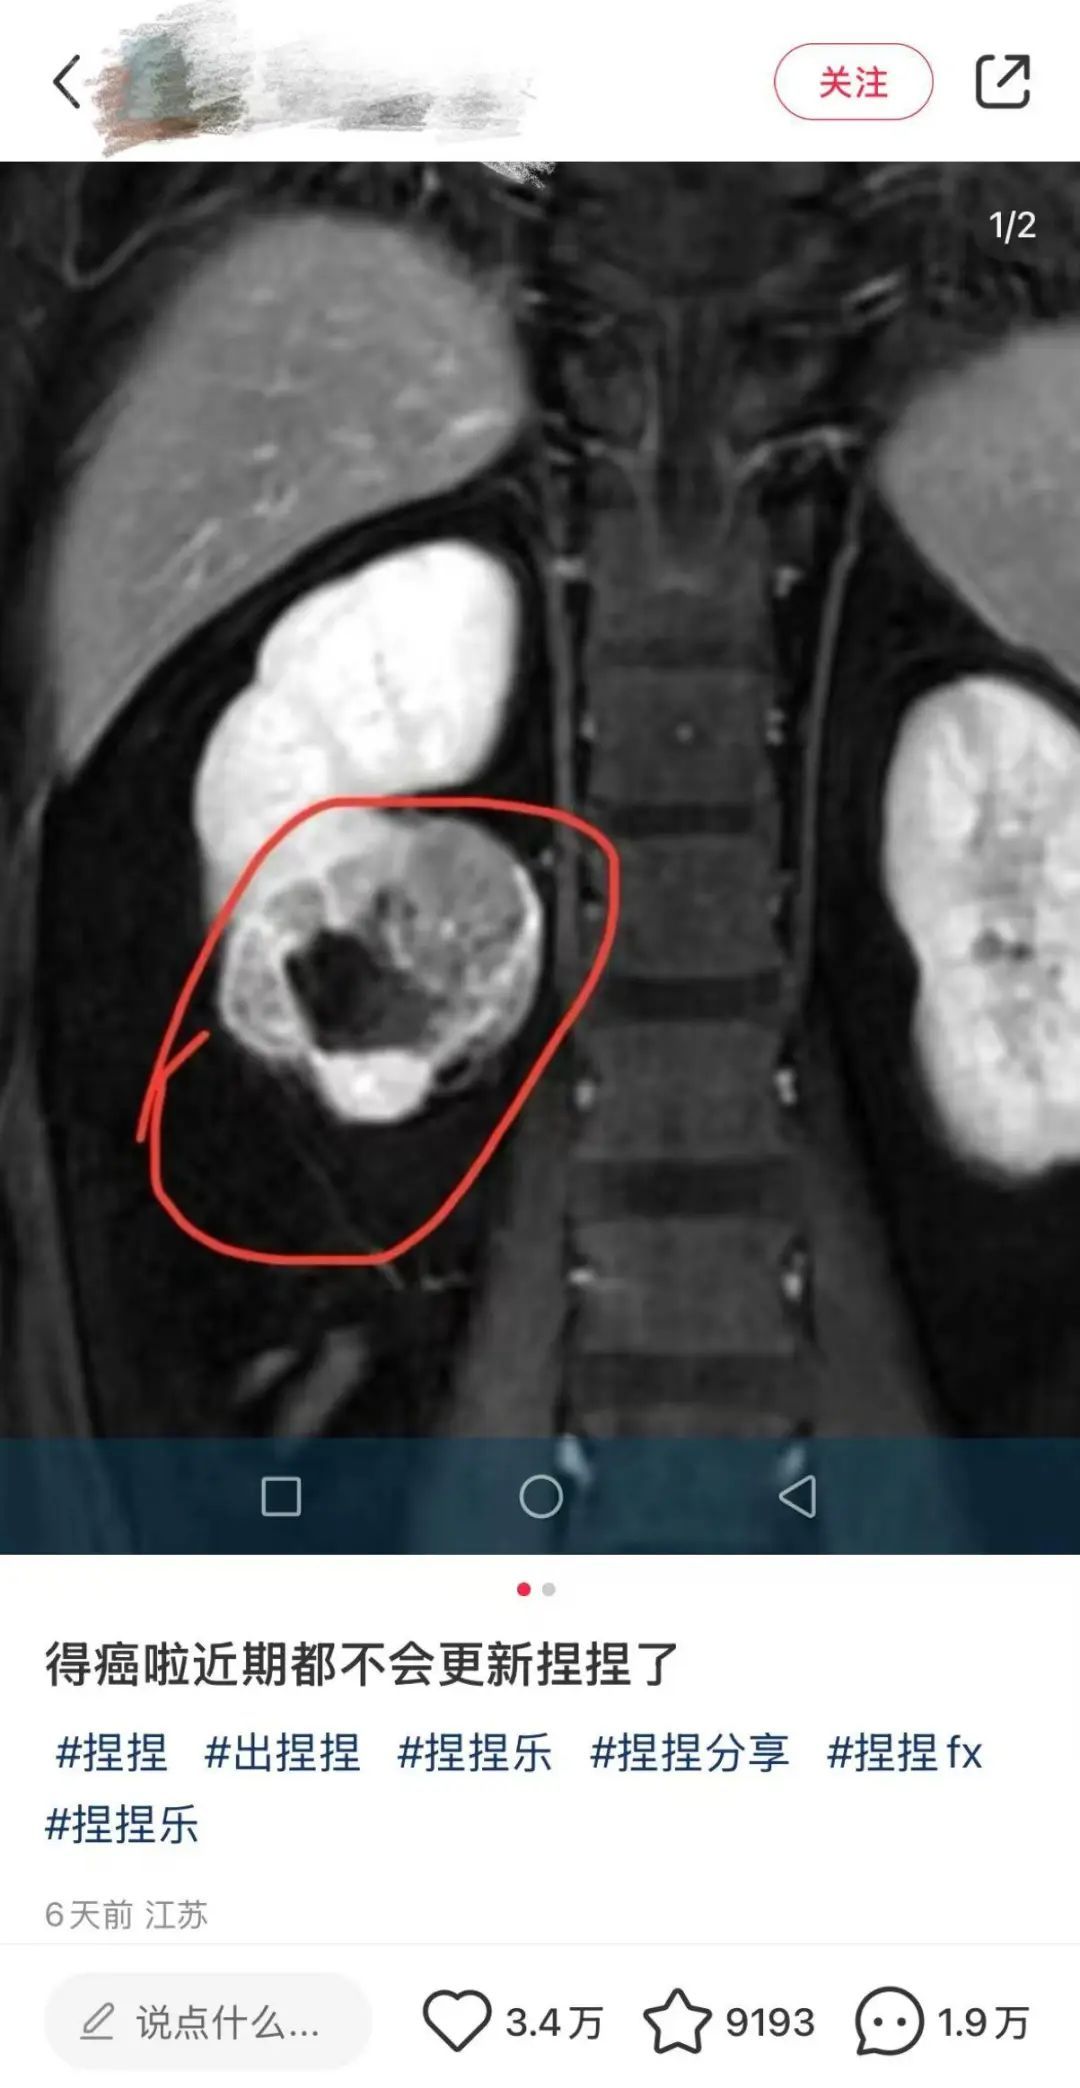

近年来,慢回弹解压玩具“捏捏乐”因柔软触感和可爱外形受到儿童及年轻人青睐。近日,某解压“捏捏”玩具博主在社交媒体上发文透露自己罹患癌症,并宣布停止更新与“捏捏”玩具相关的内容。虽然该博主并未透露患癌原因,但“捏捏乐”的安全性问题再次引起网友热议。